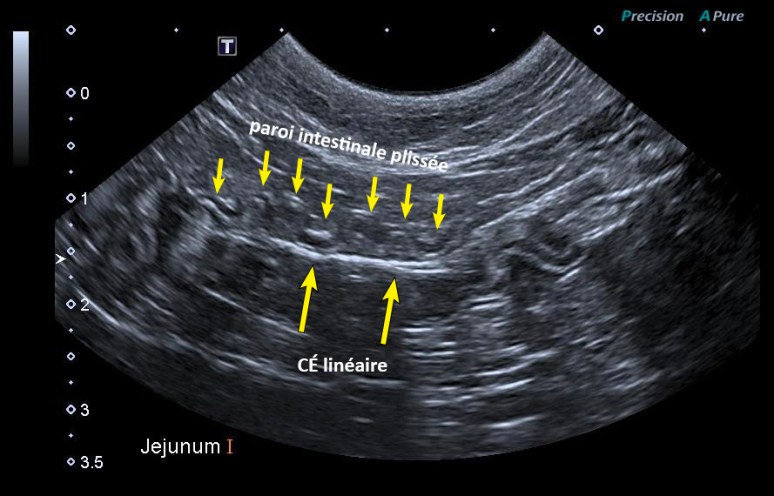

Dans le cas présent, l’échographie abdominale a été effectuée mettant en évidence un long corps étranger linéaire avec point d’ancrage dans l’antre pylorique. Le duodénum était irrégulier et légèrement distendu de liquide. Une structure hyperéchogène linéaire associée à un ombrage acoustique était visible dans la lumière du duodénum et du jéjunum, entraînant la plication statique d’une grande partie du jéjunum autour de celle-ci. Aucun signe de perforation intestinale n’a été noté. Une laparotomie exploratrice a été effectuée par la suite et un long ruban a été retiré du tractus gastro-intestinal.